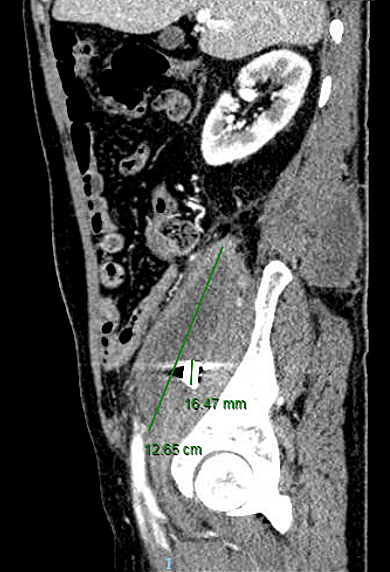

Hình ảnh mảnh đạn nằm ở vùng cơ thắt lưng chậu phải. (Ảnh: Bệnh viện cung cấp)

Qua thăm khám, bác sĩ phát hiện có một ổ áp xe to tại vùng cơ thắt lưng chậu phải và lan ra sau lưng. Sâu bên trong ghi nhận hình ảnh có một mảnh kim loại. Tình trạng bạch cầu máu của người bệnh tăng cao, dấu hiệu nhiễm trùng nặng, bác sĩ chỉ định mổ cấp cứu.

Viên đạn nằm rất sâu trong cơ thắt lưng chậu bên phải nên khả năng lấy ra rất khó. Nhưng nếu chỉ xử lý ổ áp xe mà không lấy mảnh đạn thì chắc chắn ổ nhiễm trùng sẽ tái phát", bác sĩ Lê Châu Hoàng Quốc Chương, Khoa Ngoại Tiêu hóa Bệnh viện Đại học Y dược TP.HCM, người phẫu thuật trực tiếp cho bệnh nhân, đánh giá.

Sau khi rạch phá rộng ổ áp xe, các bác sĩ đã lấy ra hơn 500 ml mủ đặc. Mảnh đạn với kích thước 1x1 cm có nhiều cạnh sắc cũng được lấy ra khỏi ổ bụng của người bệnh.